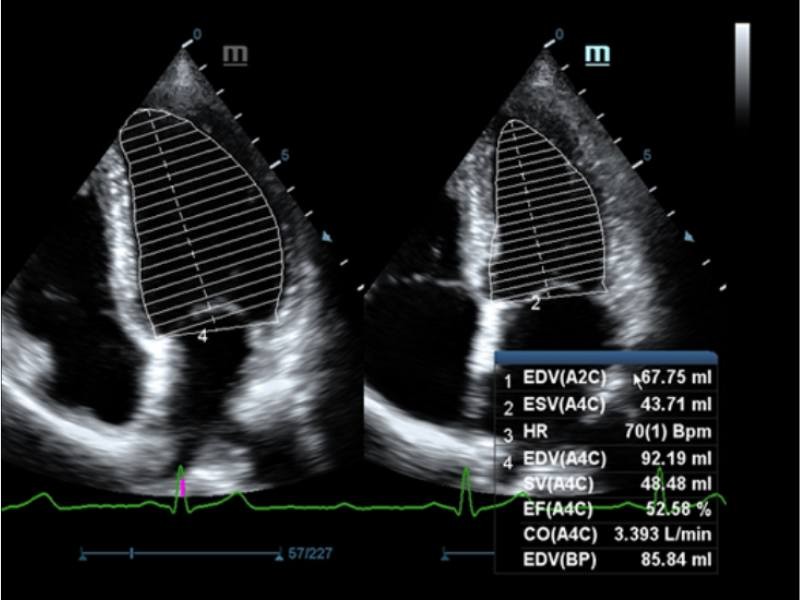

EF automático

A Auto EF é uma forma inteligente de analisar clipes de eco 2D para reconhecimento automático de quadros de diástole/sístole e os resultados de uma série de medidas para avaliar a função do ventrículo esquerdo para maior produtividade, tais como EDV/ESV/EF.